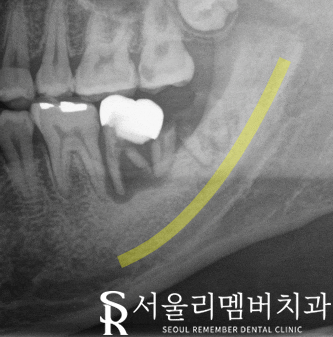

노란 선 : 하치조 신경

치관이 부러져 뿌리만 남은

37번과 그 옆 사랑니는

이를 뽑아야 됩니다.

사랑니는 교합에 방해되기

때문에 발치하였고,

37번 자리에는 임플란트(픽스처)를 심었습니다.

하악에는 하치조 신경이라는 곳이 있는데

이 부위를 피해서 식립이 이루어져야 됩니다.

저희 사당역 치과 에서는

implant 식립 시

내비게이션 임플란트 시스템을

사용해 신경 위치를 확인 후

올바르고 정확한 위치에

픽스처를 심을 수 있습니다.